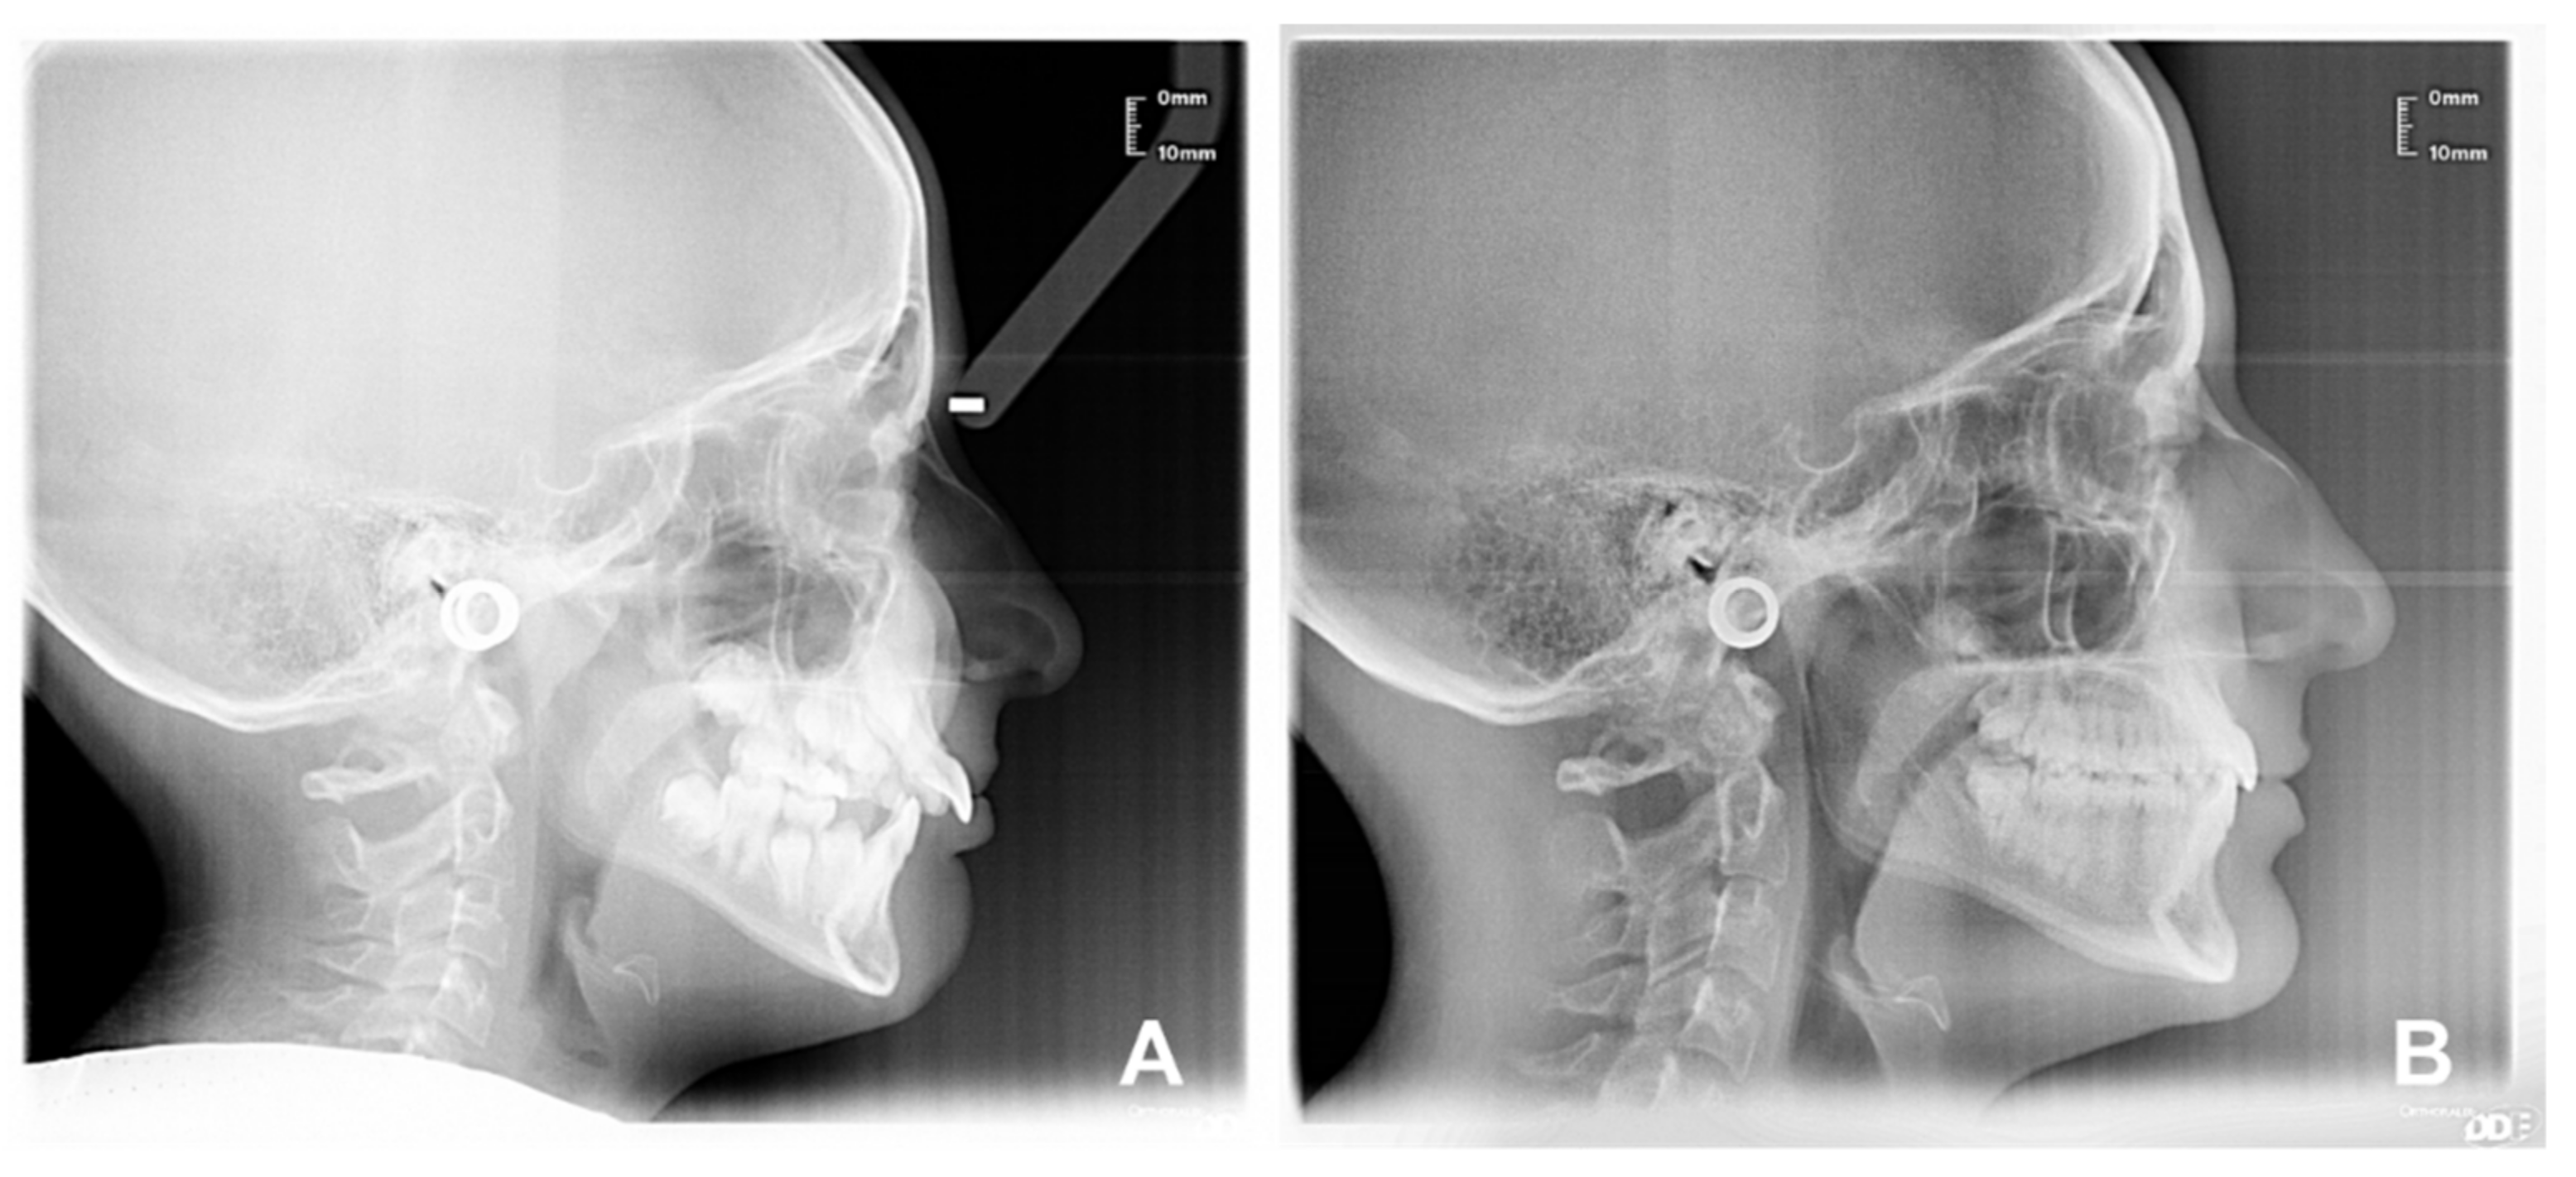

| Sagittal plane analysis: SNA (angle comprised between Sella–Nasion and Nasion point A segments) SNB (angle comprised between Sella–Nasion and Nasion point B segments) ANB (angle comprised between Nasion point A and Nasion point B segments) Vertical plane analysis: Sna-Snp^Go-Gn (intermaxillary angle, angle comprised between the bispinal plane and the mandibular plane) S-N^Go-Gn (mandibular angle, angle comprised between the Sella–Nasion segment and the mandibular plane) PFH/AFH (posterior facial height and anterior facial height ratio) Growth predictors: N-S-Ar (saddle angle comprised between Nasion–Sella and Sella–Articular segments) S-Ar-Go (articular angle comprised between Sella–Articular and Articular–Gonion segments) Ar-Go-Me (gonial angle comprised between Articular–Gonion and Gonion–Menton segments) Ar-Go-N (upper gonial angle comprised between Articular–Gonion and Gonion–Nasion segments) N-Go-Me (lower gonial angle comprised between Nasion–Gonion and Gonion–Menton) Dental analysis: Is:NA (maxillary incisor distance) Ii:NB (mandibular incisor distance) OVJ (overjet) OVB (overbite) IsIi: interincisal angle (angle between the major axis of the upper and lower incisors). Upper airway space analysis: SPAS: superior posterior airway space (distance between the soft palate and the posterior wall of the nasopharynx measured along a line parallel to Gonion–Menton (Go–Me) plane) MAS: medium airway space (distance between the lower tip of the soft palate and the posterior wall of the oropharynx measured on a line parallel to Go–Me plane) IAS Inferior Airway Space (distance between the lingual base along the mandibular Go-Me plane and the posterior wall of the pharynx) Mandible measurements Ar-Go (ramus height measured on Articular-Gonion segment) Go-Me (corpus length measured on Gonion-Menton) |